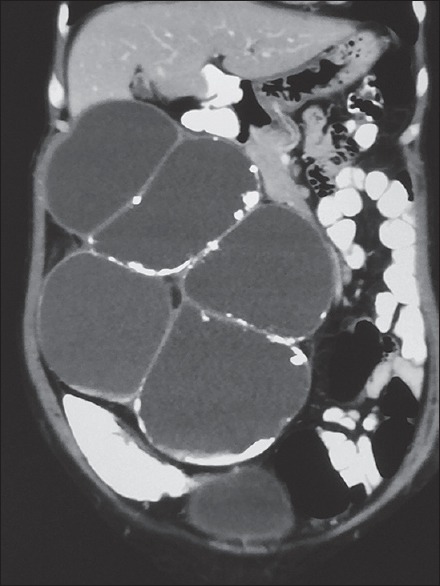

具有肉瘤样特征的肾细胞癌是一种罕见的表现,发病率为5%。肉瘤样肾细胞癌通常伴有不良预后。它通常转移到肺、骨和肝。伴有副肿瘤综合征的皮肤病表现极为罕见。肾细胞癌中PNP的发病机制尚不清楚;然而,迄今为止,很少有文献报道针对一组plakin家族的抗体,该家族在RCC的中间丝附着中起关键作用。我们报告一例64岁女性肾细胞癌合并PNP病例。

Renal cell carcinoma with sarcomatoid features is a rare presentation with a 5% incidence. Sarcomatoid renal cell carcinoma is usually associated with poor prognosis. It commonly metastasizes to the lungs, bones, and liver. Dermatological manifestation with paraneoplastic syndrome is extremely rare. Pathogenesis of PNP in renal cell carcinoma is not cleat; till date, however, few literature suggest antibodies against a group plakin family which plays a key role in intermediate filament attachment in RCC. We present PNP in a 64-year-old female associated with renal cell carcinoma.